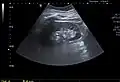

Renal cyst as seen on abdominal ultrasound